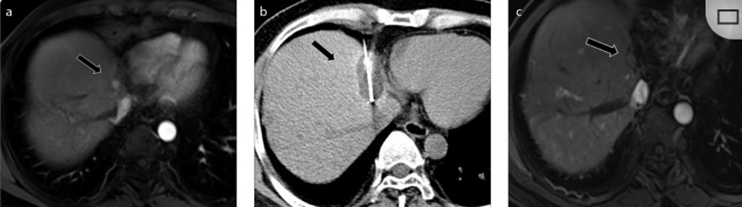

( a ) 軸向 MRI 和 ( b ) 軸向 CT 顯示肝S8段有一個16mm的病灶,鄰近肝緣。( c )冷凍消融期間CT顯示放置了2個冷凍探針,低密度冰球包圍病灶。(d)術(shù)后1個月隨訪 CT顯示冰球?qū)?yīng)的壞死區(qū)域,未見復發(fā)。(e)術(shù)后6個月的CT,壞死區(qū)域縮小,未見復發(fā)。(f)與基線影像(g)相比,12個月后的FDG-PET/CT顯示未見FDG攝取。

62歲女性,肝轉(zhuǎn)移(卵巢癌)腫瘤的完全消融病例(a)軸向CT顯示病變位置毗鄰心臟和上腔靜脈(黑色箭頭)。(b)術(shù)中軸向CT掃描:使用三個冷凍探針。1個月后的軸向(e)和冠狀位(f)增強CT掃描顯示低密度區(qū)域,由于肉芽組織反應(yīng)引起的邊緣增強。